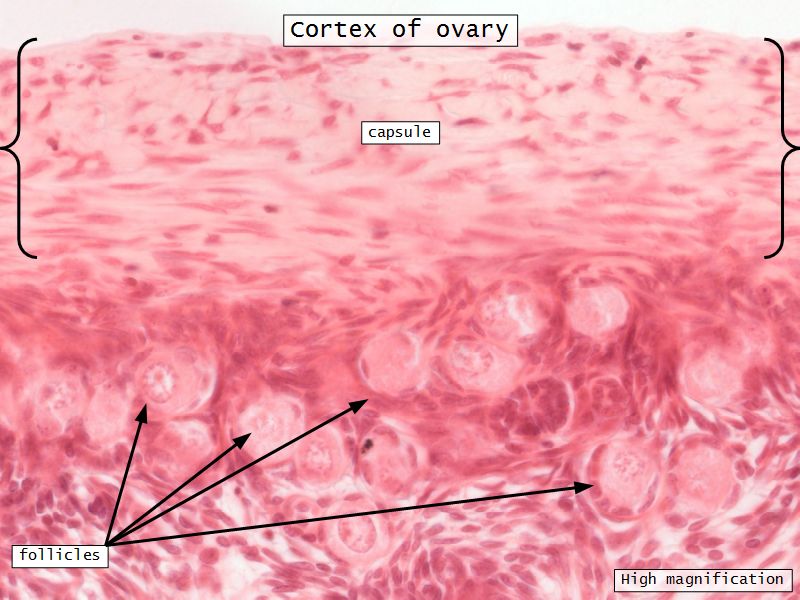

Cortex

- Tunica albuginea

- Irregular dense CT capsule

- Follicles in various phases

- Stroma containing follicles

Stroma

- Highly cellular loose CT

- Fibroblasts

- Elastic & collagen fibres

- Form layers around follicles